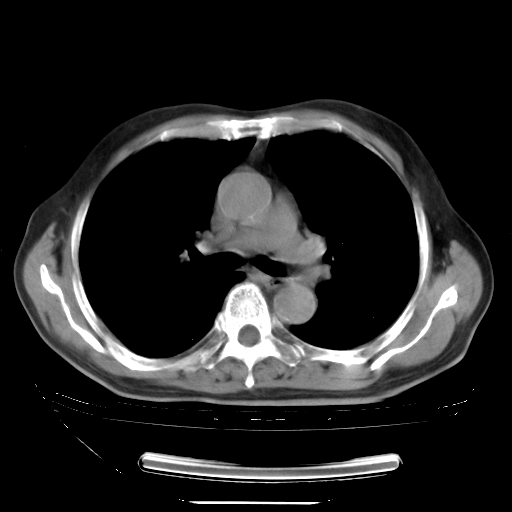

今天复查肺部CT,发现双肺广泛磨玻璃样改变。所以我把3月19日和5月9日相隔50天的肺部CT上传。请大家会诊。

2009年3月19日肺部CT片。

2009年3月19日肺部CT